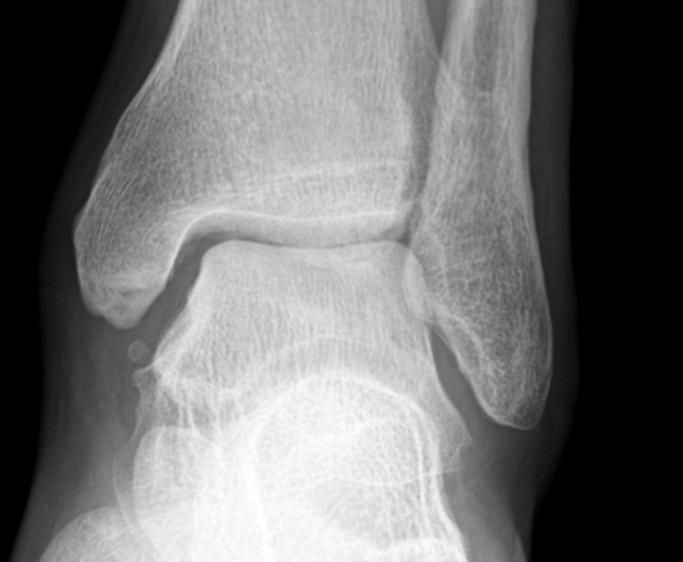

최근 발목이 아파 병원에 방문했더니 발목 관절염 초기라고 이야기해서

엑스레이 확인 후 자료 받아와 확인 해봤는데 저는 잘모르겠어서....ㅠㅠㅠ

병원 3군데 갔는데 2군데는 맞다 한군데는 애매하다는 소견을 내려주셨습니다.

혹시 엑스레이 사진상 발목 관절염이 확인 되는지 질의 드립니다.

만약 확인 되면 발목 관절염 현재 몇단계 정도 진행중인가요?

• 2번 째 사진

엑스레이상에서는 양쪽의 비교를 해보시는 것이 가장 정확하지만, 여러 의견을 들으신 것처럼 발목관절염의 초기로 보이지만, 관절에는 큰 변화가 없는 것으로 보이는데요

• 안녕하세요. 남희성 의사입니다.

애매하다고 표현하신 경우에도 다른 의사들이 관절염이 있다고 이야기하셔서 애매하다고 표현하셨지 골관절염이 아니라고 판단하셨을겁니다.

제가 보기에는 관절염 소견이 보이지 않습니다.

만약에 관절염이 맞다고 하더라도 가장 초기단계로 생각하시면 되겠습니다.